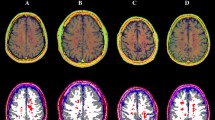

At the voxel-based analyses (Fig. 3 and Supplementary Table 1), MS patients showed massive clusters of reduced volume compared to HC, extensively encompassing both supra- and infra-tentorial GM and WM, with local maxima located in the bilateral thalami and fornices, respectively (p values < 0.001). Similarly, widespread clusters of reduced R1 values emerged in MS patients, extending well beyond the distribution of visible T2-hyperintense lesions and peaking in the corpus callosum, periventricular WM, and thalami (p values < 0.001). As for the analysis of QSM images, MS patients showed several clusters of reduced χ values compared to HC, involving the bilateral cerebral WM (particularly the frontal sections of the corpus callosum, corona radiata, superior longitudinal fasciculus, and cingulum—p values < 0.001), the midbrain (p = 0.001) and the bilateral pulvinar and right thalamic ventral lateral nucleus (p-values < 0.001), along with small clusters of increased χ values in the left body of the caudate nucleus (p = 0.004), and the right anterior cingulate (p = 0.005) and superior frontal (p = 0.02) gyri.

Results of the between-group voxel-wise comparisons. A lesion probability map (LPM), obtained by summing all the binary lesion masks and dividing by the number of patients to give a lesion probability at each voxel, is presented (with a 5% probability threshold, upper left panel), along with clusters of significant between-group difference in terms of volume (upper right panel), R1 and χ (lower panels) values for both the MS > HC (red-yellow) and MS < HC (blue-light blue) contrasts, all superimposed on axial sections of the average T1-weighted volume in the MNI space. For volume, R1, and χ maps, pooled results of the GM and WM analyses are shown. Images are in radiological orientation

Effect size (Cohen’s d) maps of between-group differences in terms of regional volume, R1, and χ values (obtained from permutation-based T statistics estimated in the TFCE toolbox) are also presented in Fig. 4.

Effect size maps of between-group differences. Effect size (Cohen’s d) maps of between-group differences in terms of volume, R1, and χ values (from left to right) are presented, superimposed on axial sections of the average T1-weighted volume in the MNI space. Positive effect size values refer to the MS < HC contrast. For volume, R1, and χ maps, pooled results of the GM and WM analyses are shown. Images are in radiological orientation